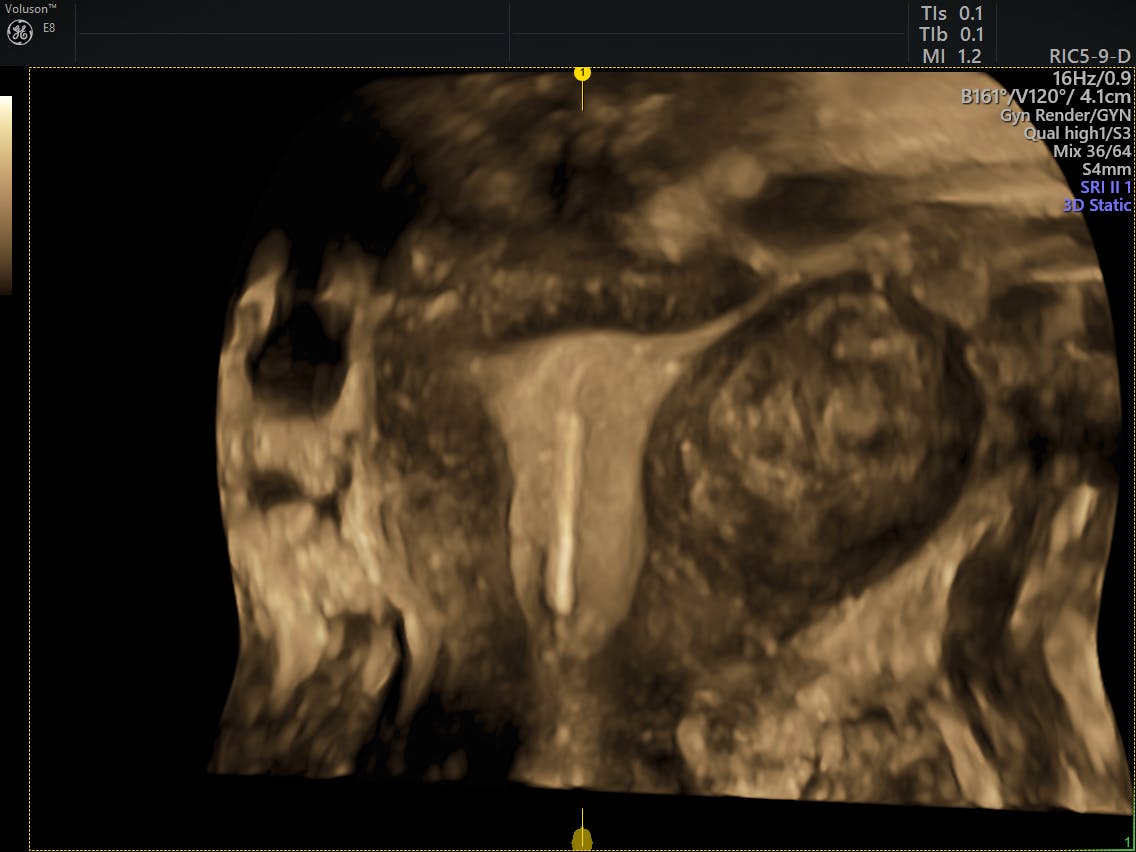

Primary indications for female pelvic us examination are pelvic pain, abnormal vaginal bleeding, and suspicion of pelvic mass. Find problems with the structure of your uterus or ovaries look for cancer in your ovaries, uterus, or bladder find an intrauterine device (iud) However, its views may be limited by abdominal structures such as bowel gas. Ultrasound very clearly visualizes the endometrial lining (figure 1) and identifies potential causes for the bleeding. An ultrasound of the pelvis is typically used to look at the bladder, ovaries, uterus, cervix, and fallopian tubes (some of these are known as the female reproductive organs).

Some women experience changes in their menstrual cycle in length or quantity. By dr attiya khan and mr rehan khan. Pelvic ultrasound is usually the initial modality for imaging gynecologic pathology, including acute pelvic pain and chronic pelvic pain. A pelvic ultrasound is the best test to examine a growth in your pelvis. However, its views may be limited by abdominal structures such as bowel gas. Fed up with deciphering jargon, dr attiya khan asked consultant gynaecologist mr rehan khan for a plain language guide to understanding pelvic ultrasounds. The uterus contains various types of cells to help women carry a baby. Ultrasound very clearly visualizes the endometrial lining (figure 1) and identifies potential causes for the bleeding. Diagnostic purposes of a pelvic ultrasound include: Imaging tests can identify abnormalities and help doctors diagnose conditions. Identifying the origin of symptoms such as pelvic pain from an unknown source, abnormal bleeding, or menstrual problems. A pelvic ultrasound is a noninvasive diagnostic exam that produces images that are used to assess organs and structures within the female pelvis. These organs include the vagina, cervix, uterus, fallopian tubes and ovaries.